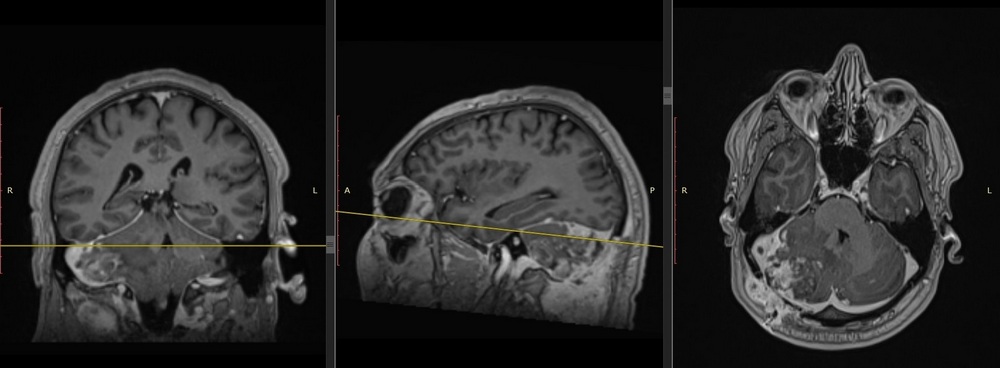

| Снимки до операции. Опухоль полушария мозжечка | Снимки МРТ послеоперационный контроль. Опухоль удалена полностью |

Благодаря применению этого подхода удалось полностью удалить опухолевые клетки не только в зоне операции, но и в прилежащих структурах головного мозга, что, в свою очередь, будет способствовать увеличению безрецедивного периода и улучшению качества жизни пациента. Послеоперационный период прошел без осложнений. На контрольных МРТ-исследованиях подтверждено тотальное удаление злокачественной опухоли головного мозга. Пациент выписан в удовлетворительном состоянии без неврологического дефицита.